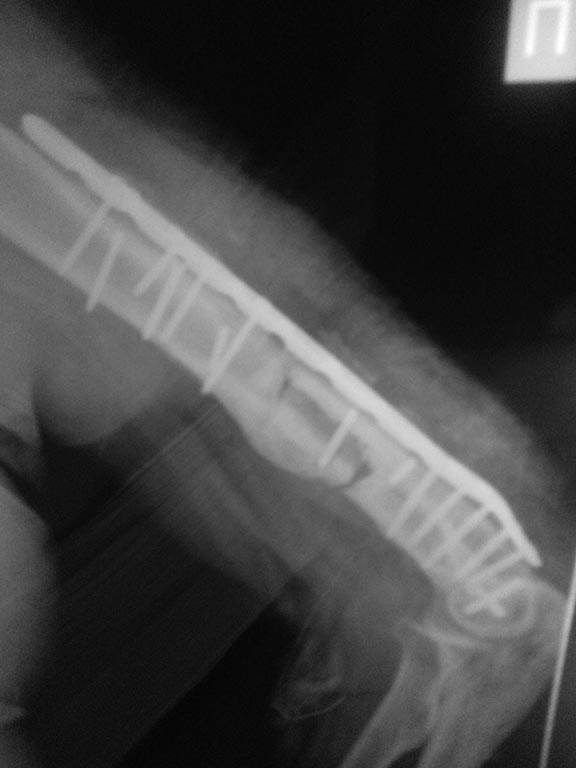

5 месяцев с АВФ боковая